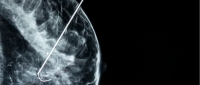

Descreveremos aqui as principais aplicações da ultrassonografia supra-púbica e transvaginal na detecção e estadiamento das formas ovariana e profunda / infiltrativa.

- Endometriose ovariana

O USTV apresenta excelente sensibilidade e especificidade no diagnóstico do endometrioma de ovário, especialmente nas lesões maiores que 2 cm. Guerriero et al., em 1998, descreveram sensibilidade de 97%, especificidade de 90% e valor preditivo positivo e negativo de 95%.

Aspecto habitual dos endometriomas no USTV:

- cisto com conteúdo espesso, apresentando múltiplos pontos de média intensidade distribuídos de forma homogênea (padrão em “vidro fosco”)

- Areas hiperecóides amorfas na periferia, sem fluxo ao Doppler e com limites mal definidos (sangue mais antigo organizado)

- Pontos hiperecóides parietais (cerca de 50% dos casos)

- Nível liquido e septos

Os diagnósticos diferenciais principais são: cistos funcionais (principalmente os hemorrágicos); abscesso e neoplasia. O aspecto do conteúdo é o critério mais importante para fazer a diferenciação entre os diversos tipos de cistos. O Doppler colorido ajuda principalmente para detectar ou descartar áreas solidas vascularizadas, que são um forte indicativo de neoplasia.

Nos casos duvidosos ao USTV a ressonância magnética é o exame indicado para prosseguir a investigação.